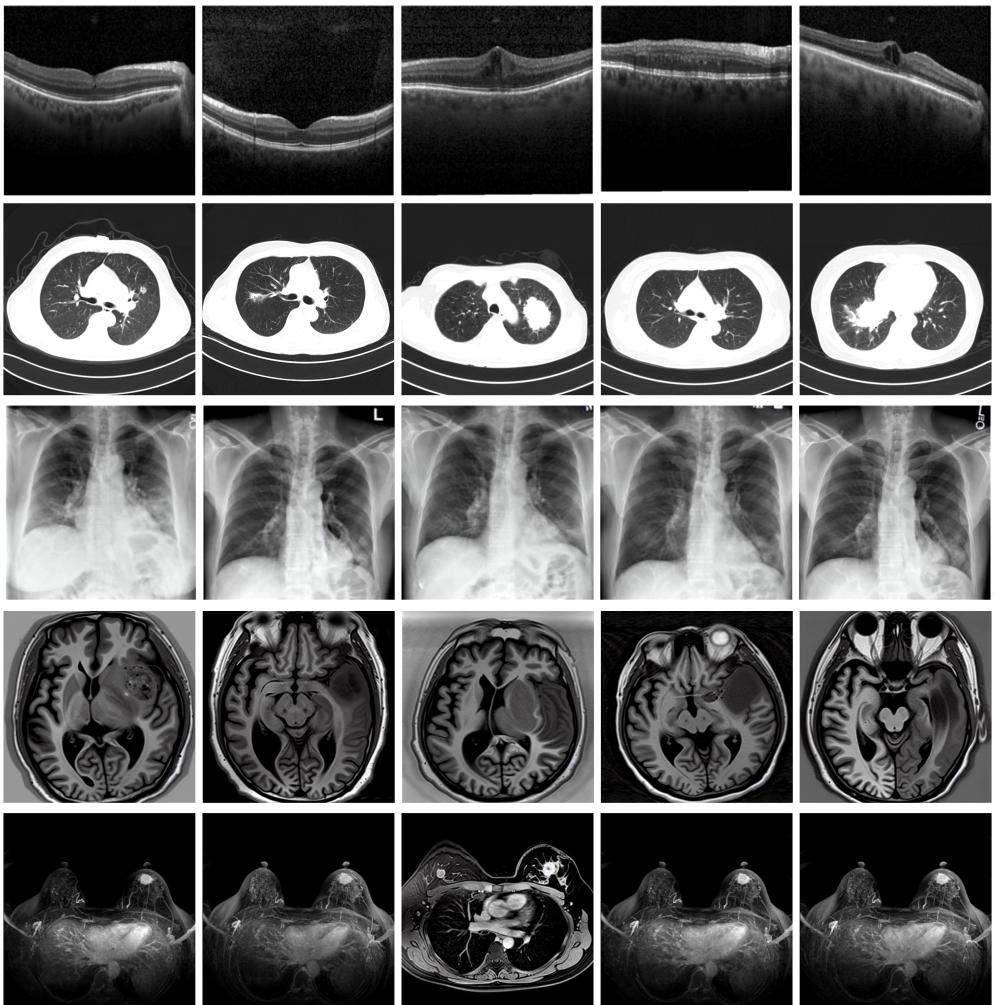

圖為由MINIM生成的高質(zhì)量醫(yī)學(xué)合成圖像(受訪者供圖)

“目前公開的醫(yī)學(xué)影像數(shù)據(jù)非常有限,我們建立的生成式模型有望解決訓(xùn)練數(shù)據(jù)不夠的問題?!北本┐髮W(xué)未來技術(shù)學(xué)院助理研究員王勁卓說,研究團(tuán)隊(duì)利用多種器官在CT、X光、磁共振等不同成像方式下的高質(zhì)量影像文本配對(duì)數(shù)據(jù)進(jìn)行訓(xùn)練,最終生成海量的醫(yī)學(xué)合成影像,其在圖像特征、細(xì)節(jié)呈現(xiàn)等多方面都與真實(shí)醫(yī)學(xué)圖像高度一致。

實(shí)驗(yàn)結(jié)果顯示,MINIM生成的合成數(shù)據(jù)在醫(yī)生主觀評(píng)測(cè)指標(biāo)和多項(xiàng)客觀檢驗(yàn)標(biāo)準(zhǔn)方面達(dá)國(guó)際領(lǐng)先水平,在臨床應(yīng)用中具有重要參考價(jià)值。在真實(shí)數(shù)據(jù)基礎(chǔ)上,使用20倍合成數(shù)據(jù)在眼科、胸科、腦科和乳腺科的多個(gè)醫(yī)學(xué)任務(wù)準(zhǔn)確率平均可提升12%至17%。